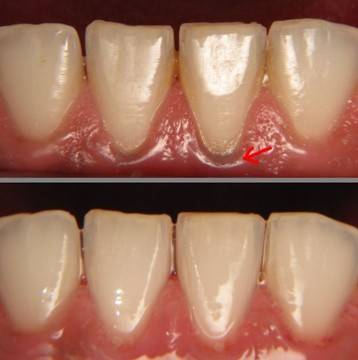

Как да решите проблема с нежелания зъбен камък , който постоянно се насъбира между зъбите ви? Освен редовното миене на зъбите и използване на зъбен конец, има още няколко алтернативни решения.